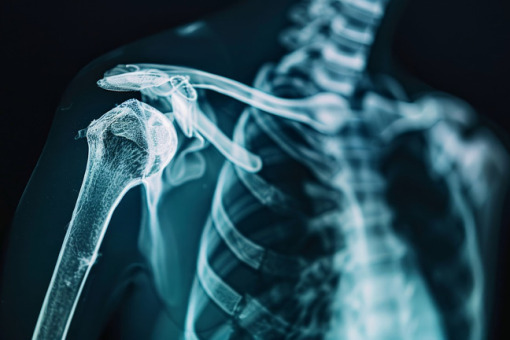

Operację rekonstrukcji panewki stawu ramiennego z wykorzystaniem przeszczepu kostnego z talerza biodrowego pacjenta wykonali lekarze w Zespole Szpitali Miejskich w Chorzowie – przekazała rzeczniczka placówki Katarzyna Hohuł. Do stabilizacji zastosowali nową metodę z użyciem taśm i kotwic.

Lekarze wykonali zabieg pacjentowi cierpiącemu na przewlekłą niestabilność barku spowodowaną dużym ubytkiem kostnym w obrębie panewki łopatki. Schorzenie prowadziło do nawracających zwichnięć stawu ramiennego określanych jako wypadanie barku. W takich przypadkach tradycyjne leczenie zachowawcze okazuje się nieskuteczne. Jedyną szansą poprawienia funkcjonowania stawu jest leczenie operacyjne.

W trakcie zabiegu lekarze pobrali fragment kości z talerza biodrowego pacjenta i wykorzystali go do odbudowy brakującej części panewki stawu. Całość ustabilizowali nowoczesnym systemem taśm i kotwic, które wspomagają integrację przeszczepu z otaczającą go tkanką kostną.